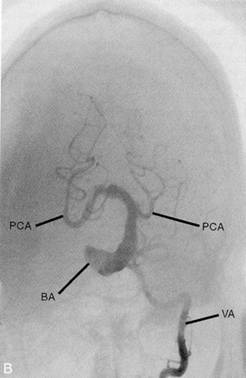

Caso 1 M. A., mulher destra de 74 anos de idade, portadora de fibrilação atrial, caiu abrupta-mente de sua cadeira, ficando impossibilitada de mover seu lado direito. Na emergência onde foi atendida, evidenciou-se uma grande hemiparesia direita associada com hemianopsia ho-mônima direita (amputação de campo visual), impossibilidade de falar e deficiência sensitiva do hemicorpo direito. Os olhos estavam desviados e paralisados conjugadamente para a es-querda. Uma tomografia computadorizada do crânio, realizada 48 horas após o evento, reve-lou uma extensa lesão isquêmica no hemisfério esquerdo, e o exame cardiológico revelou arritmia cardíaca como causa do AVC embólico da paciente. Caso 2 O Sr. A. M., de 44 anos, funcionário de uma fábrica, estava fazendo prateleiras na sua garagem, tarde da noite de um domingo, quando reparou que seu braço e sua perna esquerdos estavam um pouco fracos. Decidiu parar o trabalho, concluindo que estava provavelmente cansado demais e que era hora de ir dormir. Na manhã seguinte, a fraqueza do lado esquerdo estava muito pior. Além disso, a mão direita e a perna esquerda estavam dormentes e formi-gando. Apesar dessas dificuldades, resolveu ir trabalhar naquela manhã, porque não queria perder a festa da aposentadoria de um amigo na hora do almoço. Jurou telefonar para seu mé-dico de família, assim que ele chegasse, para ver se podia consultá-lo ainda naquela tarde. Ao longo de algumas horas, a fraqueza do Sr. A. M. se agravou. Aproximadamente às 10 horas, durante a pausa para o café, ele começou a ter dificuldade para falar. Quando tomou um gole do seu refrigerante, teve dificuldade em engolir e ele começou a tossir. Embaraçado e visi-velmente perturbado, explicou a seus colegas que sua boca “não estava funcionando direito”. Relatou nervosamente a natureza das outras dificuldades que vinha tendo nos últimos dois dias. Comiserado por sua fala visivelmente atrapalhada, um colega se ofereceu para levá-lo ao departamento de emergência do hospital próximo. O Sr. A. M. é um grande fumante (três maços por dia, há 25 anos) e um antigo forte bebedor (duas caixas de cerveja por semana). Relata que não toma mais bebidas alcoólicas, mas continua fumando. O exame físico mostra que o Sr. A. M. pesa 106,5 quilos e tem 1,78 metro de altura. Sua pressão arterial é de 180/110, com freqüência cardíaca em repouso de 93 bpm. O exame físico não apresenta outros achados. O exame neurológico revela que o Sr. A. M. estava alerta, cooperativo, e orientado quanto à pessoa, lugar e tempo. Não foram relatados testes de memória. O exame de nervos cranianos mostrou os seguintes resultados: OLFAÇÃO: não foi testada; VISÃO: campos visuais plenos à confrontação; MOTILIDADE OCULAR: não foi testada; PUPILAS: iguais e reativas ao reflexo direto e consensual à luz. A acomodação não foi testada; TRIGÊMEO: havia sen-sibilidade diminuída à picada do alfinete no lado direito da face. As respostas ao algodão e o reflexo corneano não foram testados; FACIAL: a prega nasolabial direita estava um tanto acha-tada, e a boca caía ligeiramente à direita. A motilidade das sobrancelhas não foi testada; AU-DIÇÃO: o paciente podia ouvir o esfregar dos dedos junto ao pavilhão da orelha. A audição era aparentemente normal nos dois ouvidos; VAGO GLOSSOFARÍNGEO: a voz era normal. O reflexo do vômito e o aspecto dos arcos faríngeos e da úvula não foram testados; ACESSÓRIO: não foi testado; HIPOGLOSSO: a língua desviava para a direita na protrusão. Na avaliação da Postura e Marcha, evidenciou-se que a marcha era ligeiramente atáxica, com base alargada. Incapaz de caminhar atrás de outra pessoa. Conseguia andar nos calcanhares e pontas dos pés, com difi-culdade, e precisava de apoio. A avaliação da motricidade mostrou que a força muscular estava moderadamente fraca (3/5) nas quatro extremidades. Não foram observados movimen-tos anormais. A investigação dos sistemas sensoriais mostrou estar a sensibilidade diminuída à picada de alfinete em todo o lado esquerdo do corpo. A percepção da vibração e da posição das articulações esta intacta bilateralmente. Todos os reflexos de estiramento muscular esta-vam aumentados. O sinal de Babinski estava presente bilateralmente. Havia alguma dismetria nos testes dedo-nariz e calcanhar-joelho, bilateralmente, e disdiadococinesia bilateral. O lado direito estava pior que o esquerdo. A ressonância magnética do crânio (RMC) da cabeça reve-lou que as artérias basilar e vertebral direita eram tortuosas e dilatadas. Foi notado um aneu-risma fusiforme, da porção média à porção superior da artéria basilar, com trombose intralu-minal. Não foi demonstrado sangue extravascular. Evolução: Bem cedo, no outro dia pela manhã, o Sr. A. M. teve vertigem, náusea e vômitos, de instalação súbita. Não podia mais ouvir no ouvido direito. O exame neurológico revelou nistagmo espontâneo do lado esquerdo. No dia seguinte, a audiometria confirmou a perda total da audição à direita. Foi solicitada outra RMC (Figura A). Além das anormalida-des vistas na primeira RMC, a última mostrava duas áreas de sinal diminuído na ponte, ao nível do pedúnculo cerebelar médio. Uma área de sinal diminuído ficava na linha média, a outra estava à direita. Dois dias depois, foi feita uma angiografia cerebral (Figura B). O exame demonstrou alargamento acentuado das artérias basilar e vertebral direita. Também havia evidências de aneurisma fusiforme da artéria basilar com trombose intraluminal. O aneurisma foi considerado inoperável. Foram prescritos ao paciente medicamentos anticoagulantes e terapia ocupacional. Foi aconselhado a deixar de fumar. Ao acompanhamento, dois meses depois da alta (três meses após os sintomas iniciais), o paciente havia melhorado muito. Não fumava mais e havia perdido 15 quilos. Sua pressão arterial era de 130/90 e apresentava 81 bpm cardíacos em repouso. Ainda tinha a perda total da audição no ouvido direito, mas os déficits cerebelares estavam muito melhores. Tinha perda residual moderada da sensibilidade à picada de alfinete do lado esquerdo do corpo. Todos os reflexos de estiramento muscular estavam aumentados, e ele apresentava sinal de Babinski bilateralmente. O diagnóstico defini-tivo foi de aneurisma da artéria basilar e de AVC isquêmico de tronco encefálico.